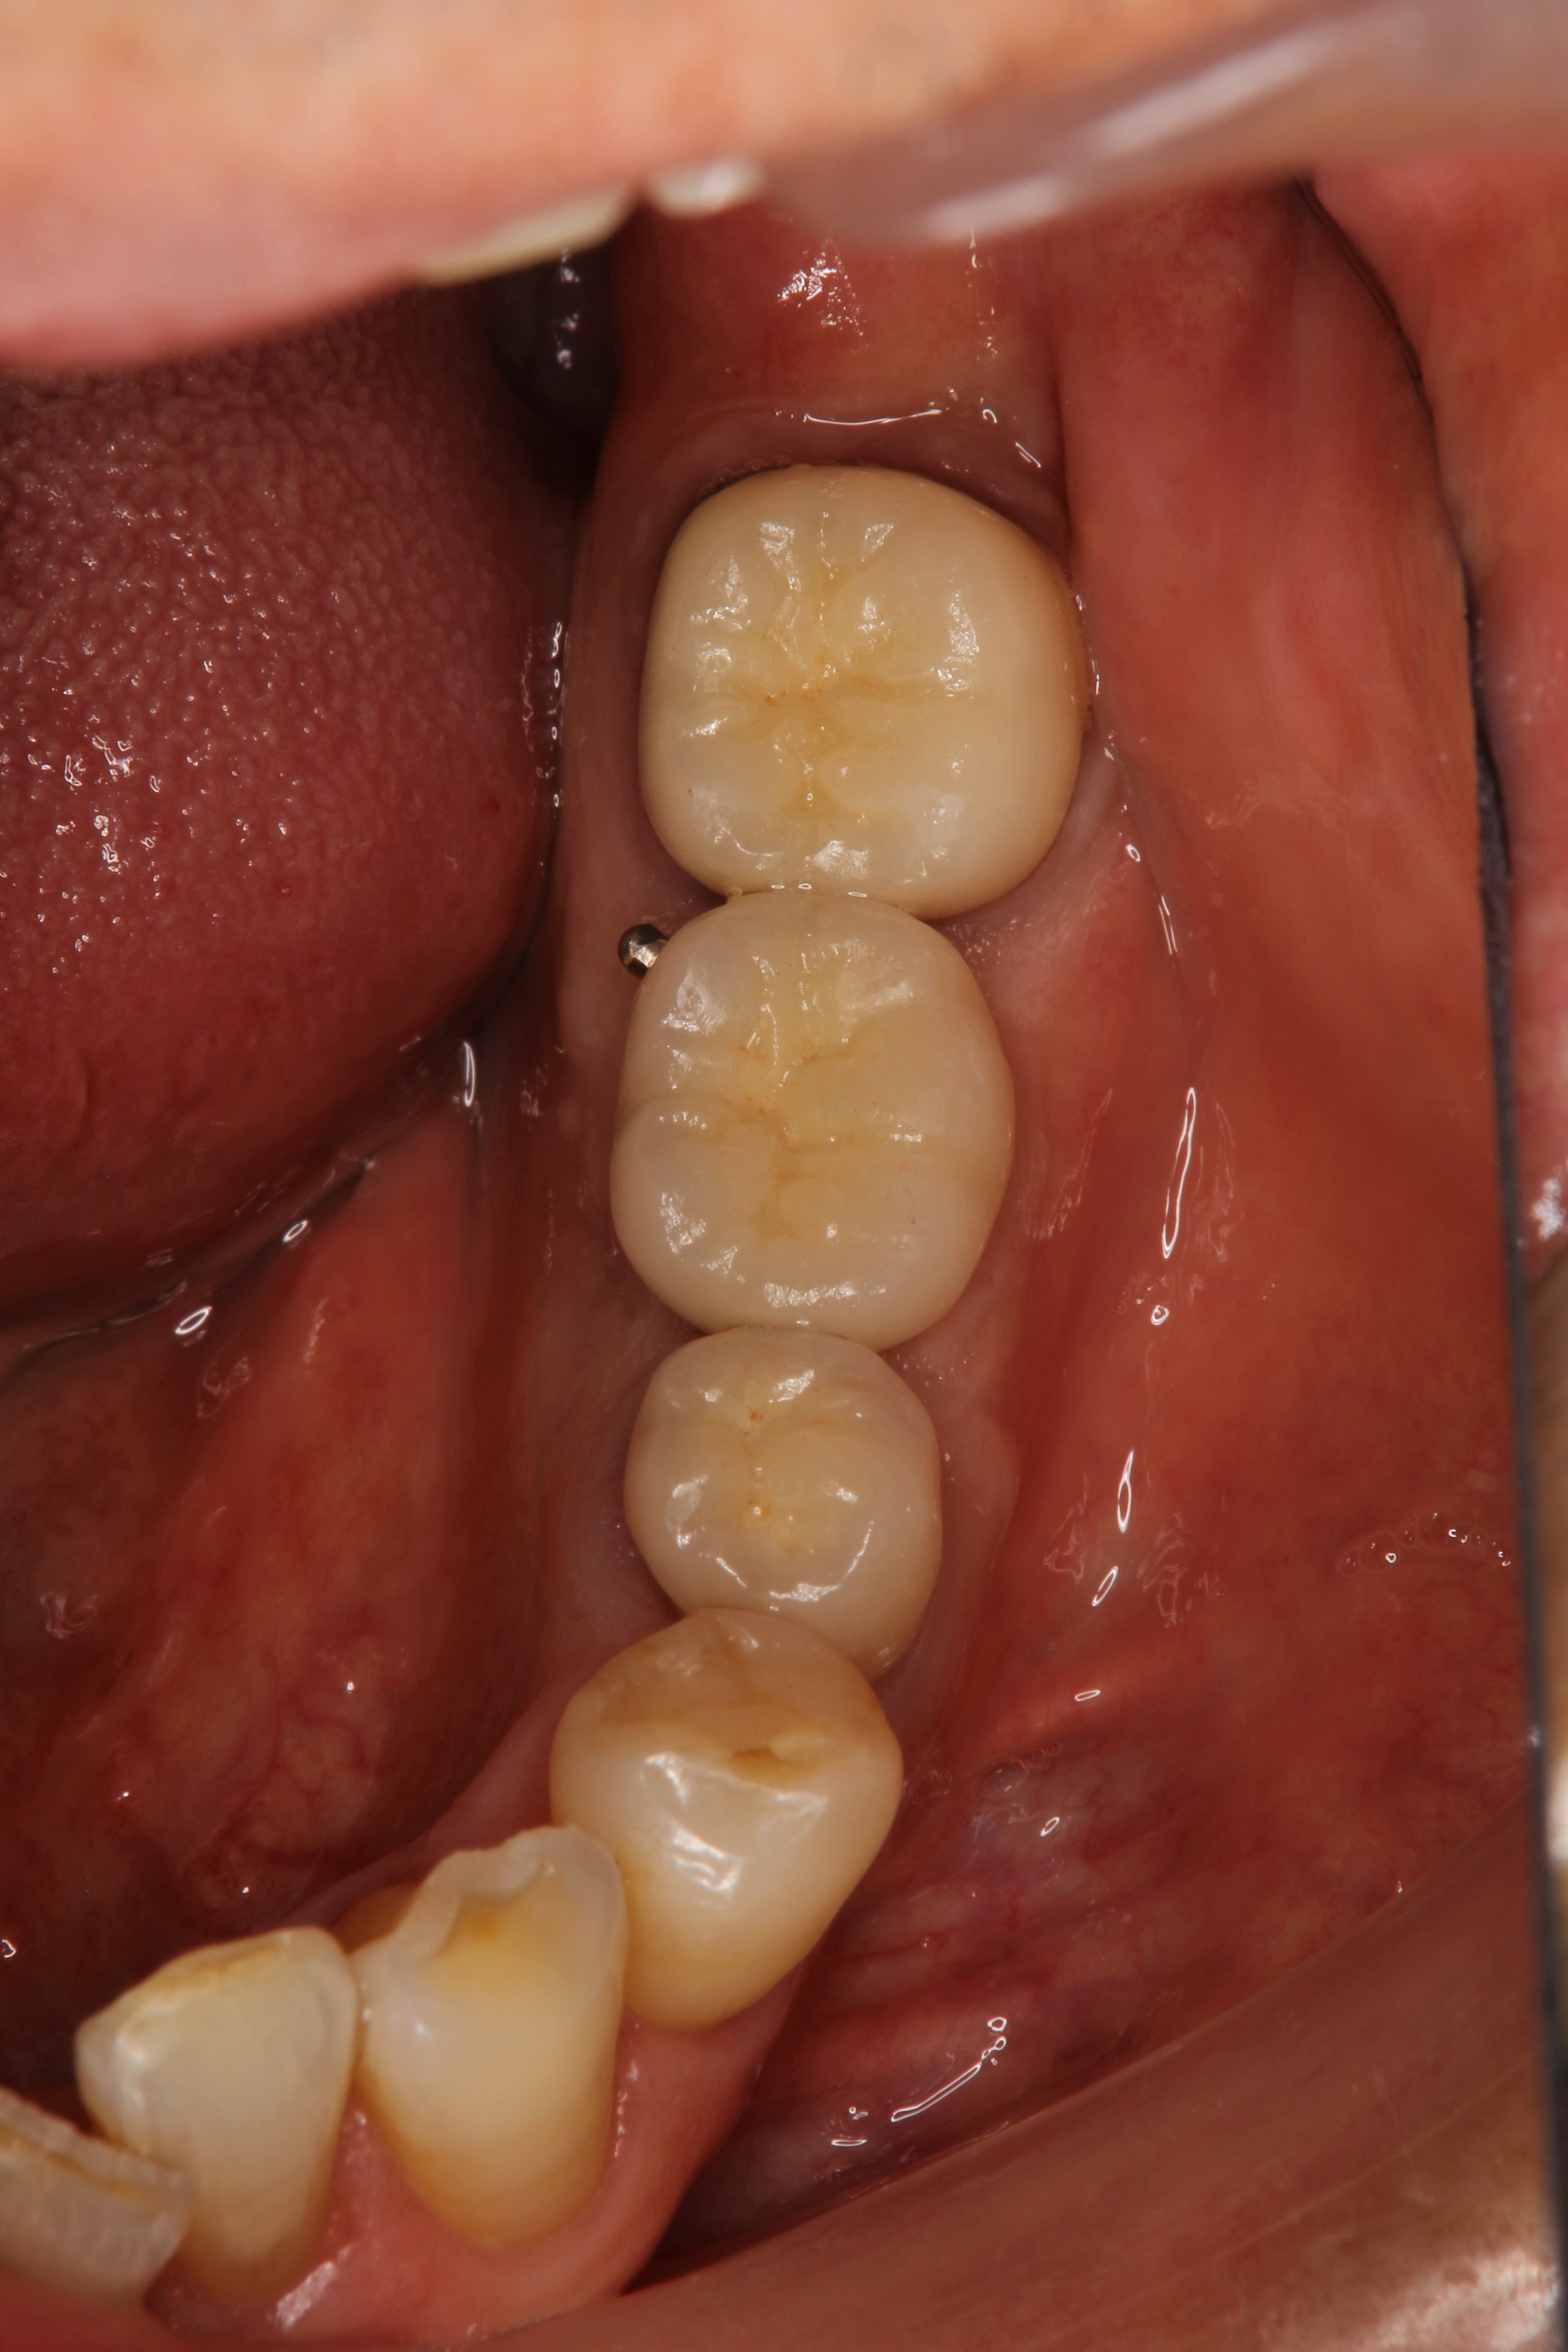

そして最後は、メタルセラミックスクラウンの装着です。

インプラントを含む3歯の治療後です。

歯冠形態(歯の形)・歯肉のラインも調和していると思います。